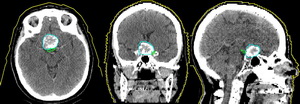

Трехмерный массив топометрической информации, полученный при компьютерной томографии, в цифровом виде вводится в систему планирования облучения. Врач-радиолог оконтуривает (сегментирует) на каждом КТ срезе мишень облучения (голубой цвет – внутричерепная опухоль) и критические структуры-органы (зеленый цвет – зрительные нервы).

По этим данным система планирования генерирует трехмерные модели очерченных структур. Врач-радиолог выбирает значение и количество направлений облучения (обычно используется от 2 до 7). С помощью имеющейся в программе функции «beam¢s-eye-view» («взгляд на мишень со стороны пучка») и цифровых симулированных рентгенограмм для каждого направления облучения определяется и очерчивается протонный пучок определенной формы в поперечном сечении. Изготовление фигурных коллиматоров и болюсов Терапевтический протонный пучок при реальном облучении формируется с помощью индивидуального коллиматора из сплава Вуда, а для придания конформности дозного распределения протонного пучка по глубине форме мишени рассчитываются и затем изготавливаются так называемые болюсы – замедлители сложной формы, учитывающие гетерогенную структуру тканей и органов пациента, расположенных на пути пучка.